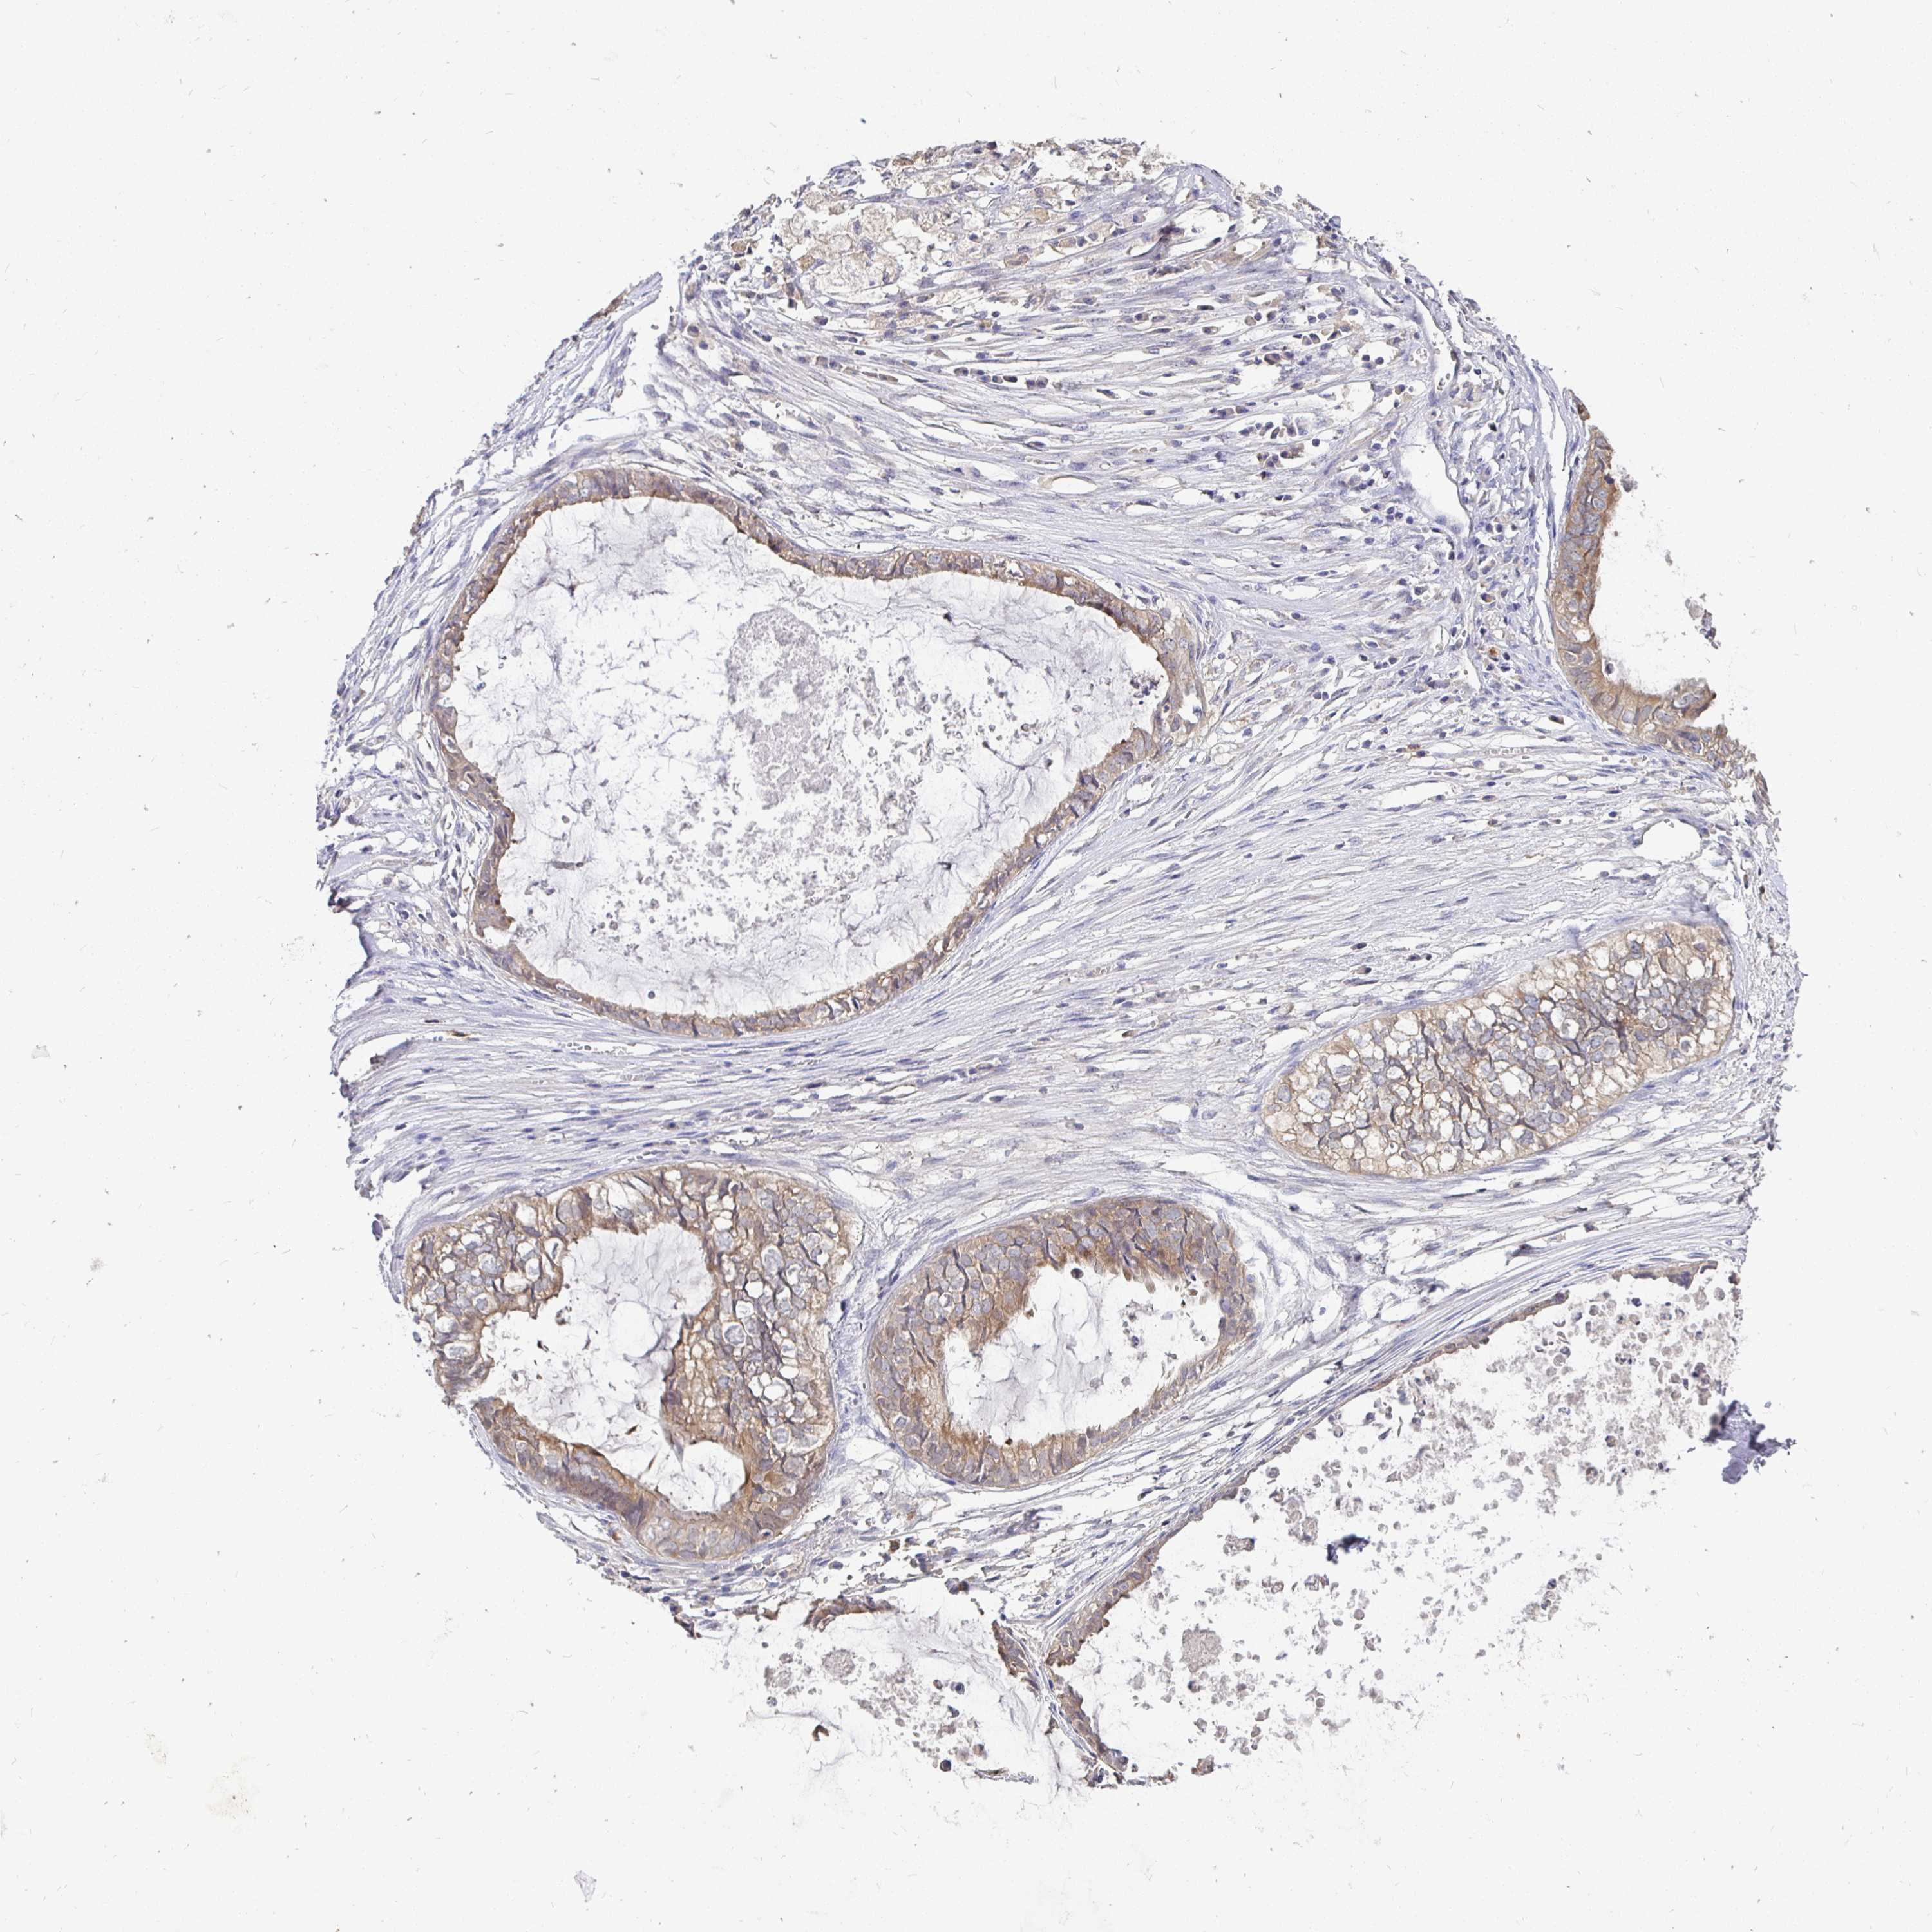

OVARIAN CANCER - Protein expressioni

A mouse-over function shows sample information and annotation data. Click on an image to view it in a full screen mode. Samples can be filtered based on level of antibody staining by selecting one or several of the following categories: high, medium, low and not detected. The assay and annotation is described here.

Note that samples used for immunohistochemistry by the Human Protein Atlas do not correspond to samples in the TCGA dataset.

Antibody stainingi

Antibody staining in the annotated cell types in the current human tissue is reported as not detected, low, medium, or high, based on conventional immunohistochemistry profiling in selected tissues. This score is based on the combination of the staining intensity and fraction of stained cells.

Each image is clickable and will lead to virtual microscopy that enables deeper exploration of all samples and also displays staining intensity scores, fraction scores and subcellular localization as well as patient and tissue information for each sample.

Antibody HPA058432

Antibody CAB022079

Adenocarcinoma, NOS